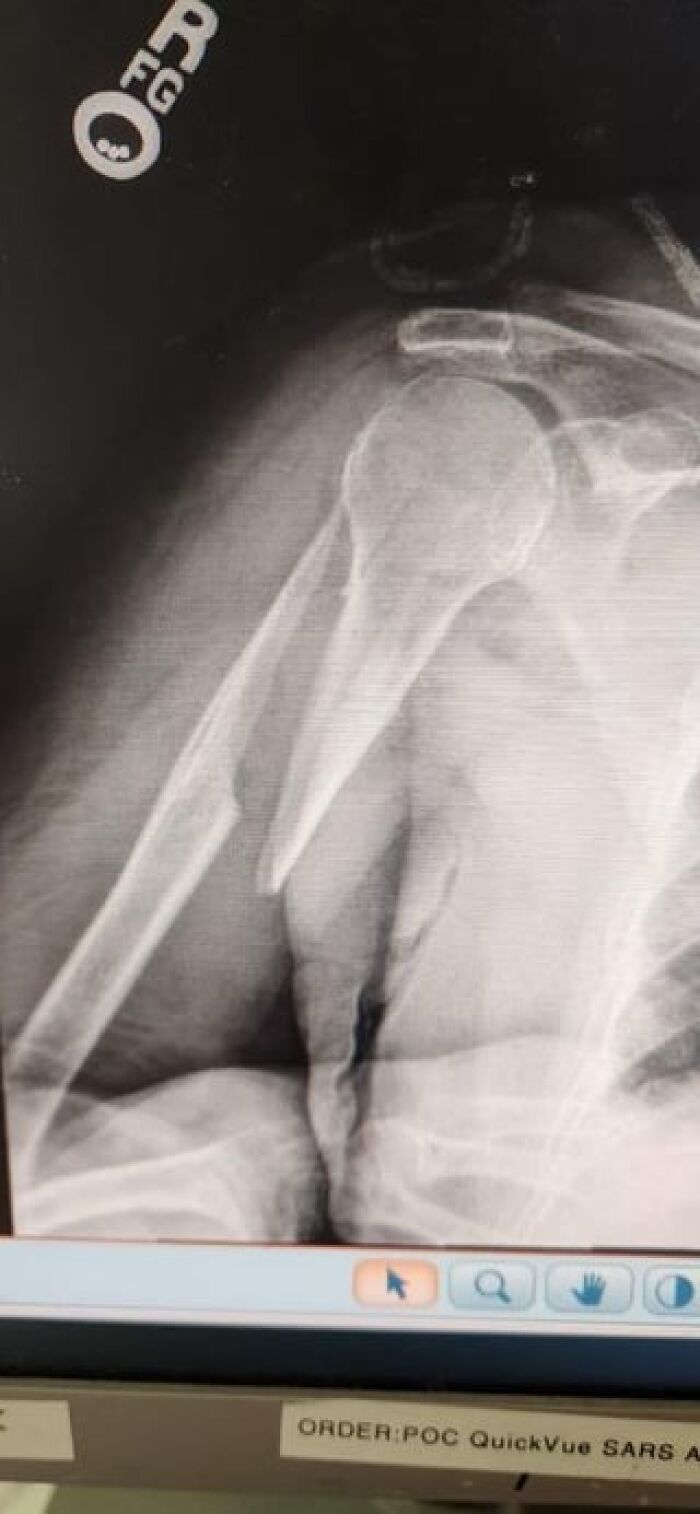

#25 My 9 Year Old Daughter Broke Her Arm. The Doctor Said She Will Heal Fine. Should I Get A Second Opinion?

Image credits: medical